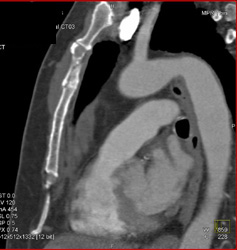

Stress Fracture